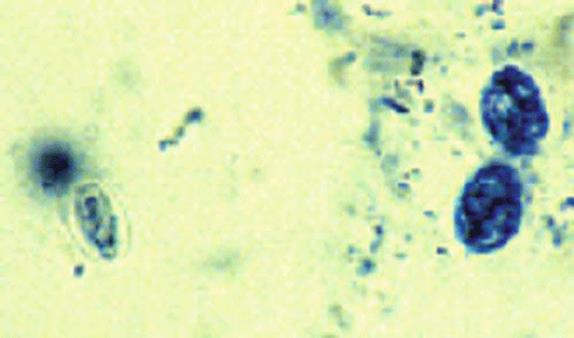

Giardia intestinalis (also known as G. lamblia or G. duodenalis) is an intestinal flagellated protozoan. The trophozoite (Fig. 31.1) is pear shaped, and the ventral surface is modified into an adhesive disc by which it attaches to the epithelium of the duodenum and jejunum. There are two oval nuclei and eight flagella. The trophozoites multiply by binary fission. Some pass down the small intestine and encyst. It is the cyst (Fig. 31.2) that is the infective stage. Cysts are passed out in the feces, and, after ingestion by the host, they excyst shortly after entering the upper small intestine. Two small trophozoites emerge from the cyst, divide, and become normal trophozoites.

Figure 31.2.

Cysts of Giardia intestinalis.